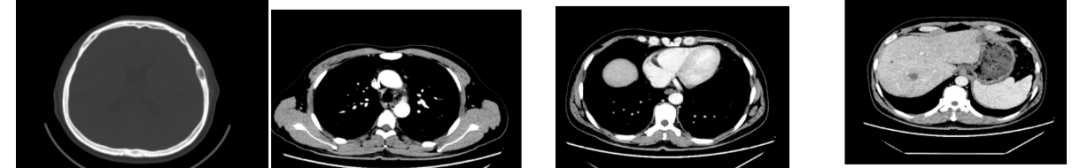

2020年4月复查:持续PR

增强CT示:肝硬化

肝异常强化灶

胃癌并肝转移化疗后,肝内转移灶大致同期;

右肺中叶外侧段、左肺上叶下舌段及右肺下叶后基底段慢性炎症;

右肺上叶前段实性微小结节,炎性结节?建议定期复查;

纵隔淋巴结转移瘤,复查大致同前。